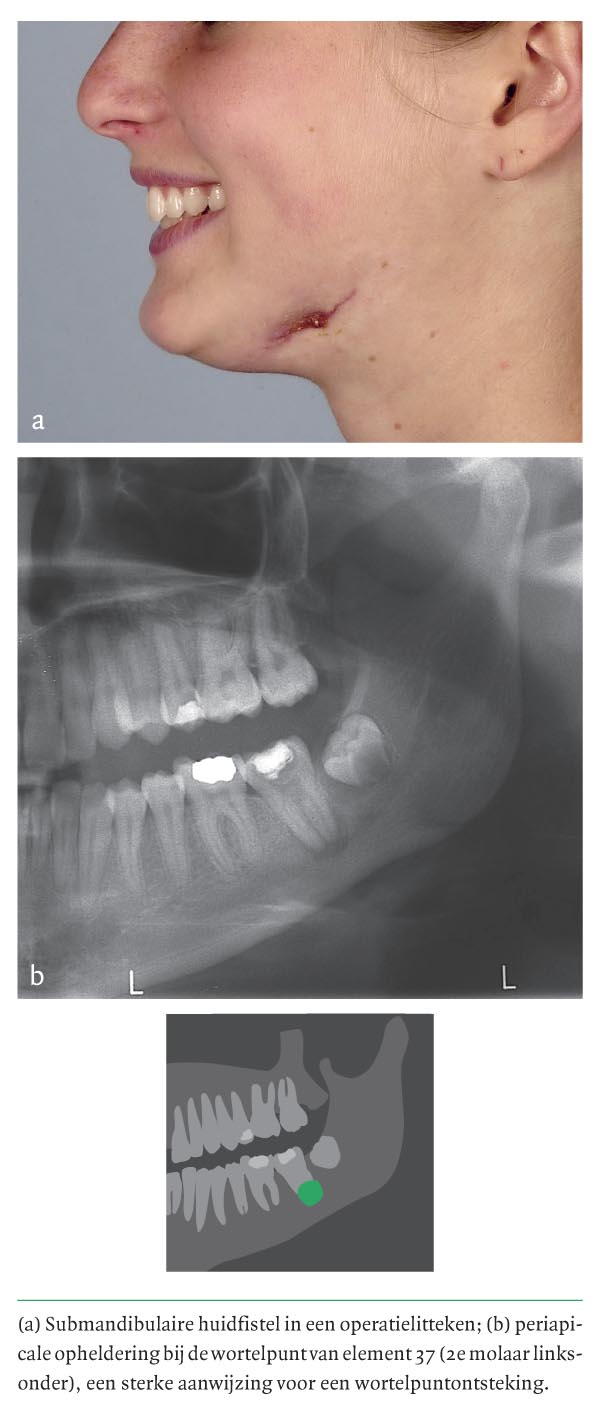

Een 17-jarig meisje had sinds ruim een half jaar een linkszijdige, wisselend pijnlijke, submandibulaire zwelling. Door de huisarts voorgeschreven antibiotica hadden geen effect. Echografisch onderzoek, diverse puncties, microbiologisch alsook histologisch onderzoek lieten bij herhaling een niet nader classificeerbaar lokaal ontstekingsbeeld zien. Kweken op mycobacteriën en Actinomyces waren negatief. Al 2 maal was de afwijking na chirurgische drainage gerecidiveerd. Bij lichamelijk onderzoek was er links een submandibulair litteken met centraal een ulcererende fistelopening die in de richting van de onderkaak liep (figuur a). Bij intraorale inspectie was het gebit gesaneerd. Element 37 (de 2e molaar linksonder) bevatte een…